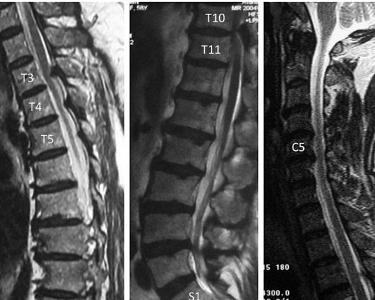

随着脊柱外科手术的广泛开展,从大量临床病例观察中发现颈椎、胸椎及腰椎黄韧带骨化症在临床上并非少见,尤其是有了CT及MRI这两种先进技术后,诊断率及发现率明显提高。其中不乏对脊髓构成压迫或刺激的病例,病情严重者则需手术切除治疗。颈椎黄韧带骨化症已列专节讨论。